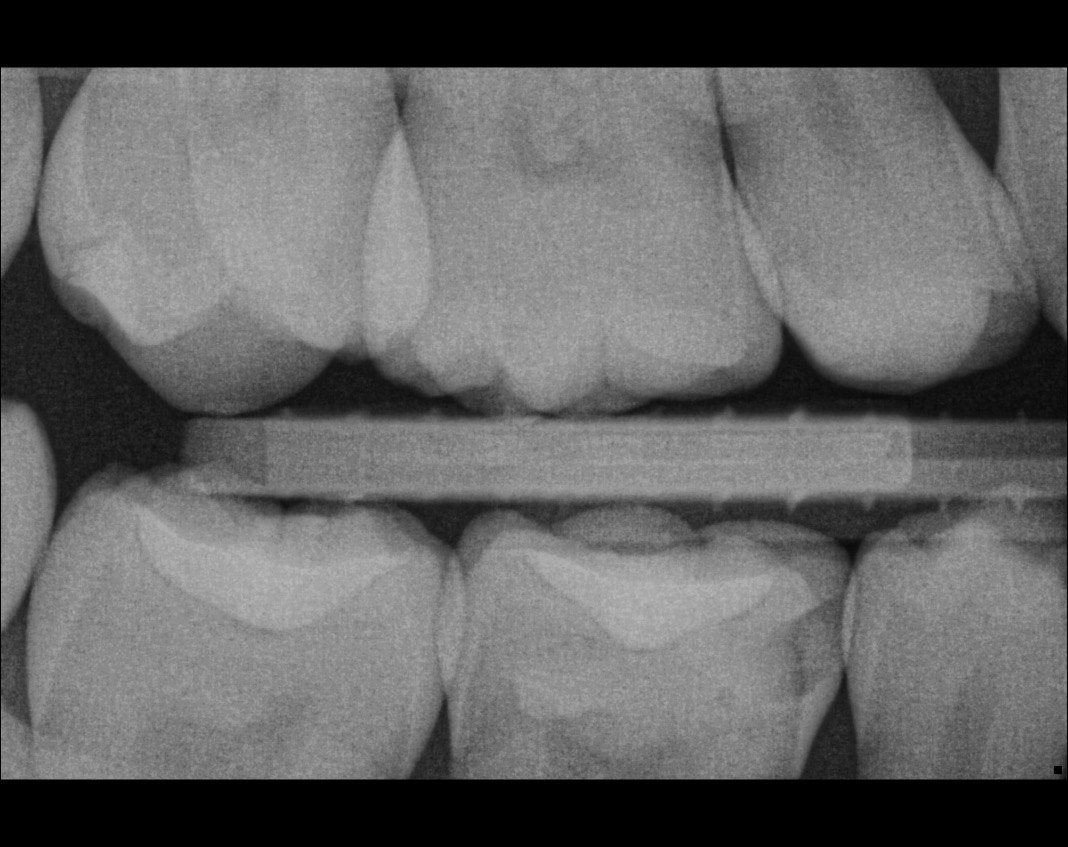

Question 24: Which condition can be detected in the following X ray?